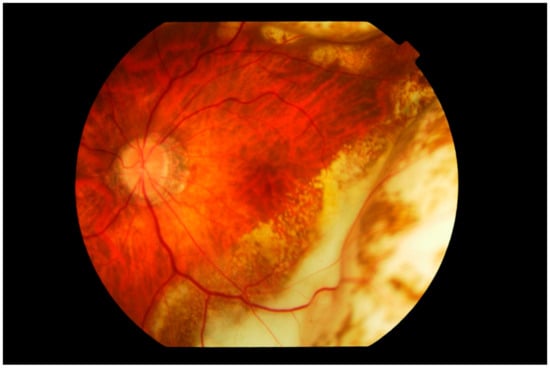

3. Clinical Features

Differential Diagnosis

4.1. Imaging

4.1.3. Fluorescein Angiography